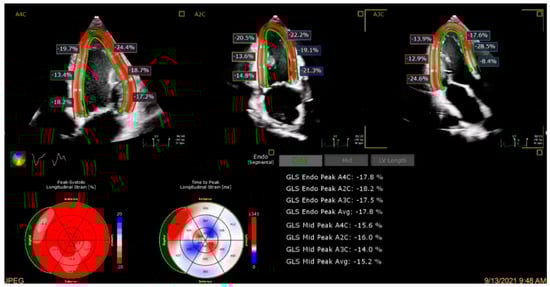

4.2. Global Longitudinal Strain

- Jiang, J.; Liu, B.; Li, Y.W.; Hothi, S.S. Clinical service evaluation of the feasibility and reproducibility of novel artificial intelligence based-echocardiographic quantification of global longitudinal strain and left ventricular ejection fraction in trastuzumab-treated patients. Front. Cardiovasc. Med. 2023, 10, 1250311. [Google Scholar] [CrossRef]

- Demissei, B.G.; Fan, Y.; Qian, Y.; Cheng, H.G.; Smith, A.M.; Shimamoto, K.; Vedage, N.; Narayan, H.K.; Scherrer-Crosbie, M.; Davatzikos, C.; et al. Left ventricular segmental strain and the prediction of cancer therapy-related cardiac dysfunction. Eur. Heart J. Cardiovasc. Imaging 2021, 22, 418–426. [Google Scholar] [CrossRef] [PubMed]

- Kuwahara, A.; Iwasaki, Y.; Kobayashi, M.; Takagi, R.; Yamada, S.; Kubo, T.; Satomi, K.; Tanaka, N. Artificial intelligence-derived left ventricular strain in echocardiography in patients treated with chemotherapy. Int. J. Cardiovasc. Imaging 2024, 40, 1903–1910. [Google Scholar] [CrossRef]